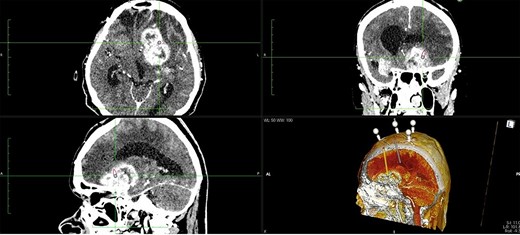

The patient underwent frameless brain biopsy using the RONNA robotic system as described previously obtaining tumor tissue for pathohistological analysis [3, 7, 8]. Using RONNAplan software two trajectories were planned, one for brain biopsy on the left side and one for EVD implantation in the right side (Fig. 2). After skin perforation, twist drilling with a 4.5-mm drill, and electrocoagulation, an EVD catheter was placed in the right lateral ventricle and clear cerebrospinal fluid was obtained under elevated pressure (Fig. 3). The total operative time, including trajectory planning and surgical procedure, was 65 min.

Two separate trajectories were planned using RONNAplan software, for brain biopsy and for EVD implantation. The plan is presented in three planes with 3d reconstruction model in right lower quadrant. Orange trajectory is for brain biopsy, whereas grey one is for EVD implantation.